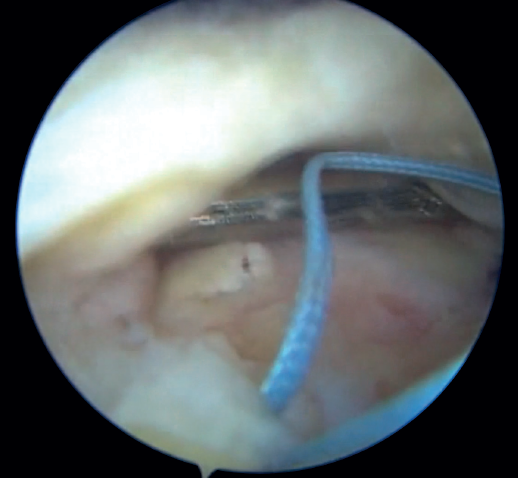

At the free margin of the tendon, four Loop Lasso®stitches are applied, according to the technique described by Lafosse(12). These stitches are made with each of the four strands of the two anchors of the second row, passing through the tissue using Curve®direct grasping forceps(Smith & Nephew Inc., Andover, MA, USA). Normally, the stitches are applied from posterior to anterior, always following the same order to avoid confusing them.

Then, the tendon is crossed 1 cm from its free margin with each of the 8 strands of the four sutures of the two anchors of the first row. The same Curve®direct grasping forceps are used for this purpose.